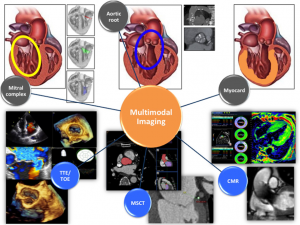

SHD治療とMultimodality imaging

私はSUNRISE YIAの際のプレゼンテーションにもあった通り、“治療に直結するMultimodality imaging”の専門家になりたいと考えており、その視点からレビューをまとめたいと考えております。

まず初回はSHD領域におけるMultimodality imagingの総論から始めていきたいと思います。作成にあたり、いくつかのReview articles (1,2)を参考にさせていただきました。

日本を含めた先進国において、弁膜症を中心としたStructure heart disease (SHD)は高齢化に伴い問題となっている。リウマチ性弁膜症が減少する一方、加齢変性による弁膜症(Degenerative valvular heart disease) の割合が増加している。TAVR, MitraClip®を中心としたのカテーテル治療の進歩に伴い、弁膜症における画像診断の果たす役割は大きく様変わりしている。

術前評価による適応患者の選択はもちろん、それぞれのModalityの特性を生かした機能的/構造的評価とその利点, 欠点について理解することが必要な時代となっている。

2. 心臓超音波検査

心臓超音波検査(以下心エコー)はSHD領域イメージングにおける根幹を担っている。インターベンションにおいても術前、術中、術後に経時的に行うことが可能であり、日常診療において欠くことのできないModalityである。その汎用性、低リスク、低コストなどの面に関しては特筆すべきものがある。ほとんど禁忌となる患者は存在せず、ESC/EACTS弁膜症ガイドライン (3)においても心エコーは弁膜症診療におけるKey techniqueと位置付けられている。

一般的な経胸壁心エコー(TTE: transthoracic echocardiography)に加え、経食道心エコー(TEE: transesophageal echocardiography)、薬物/運動負荷心エコー、ストレイン解析などを活用することにより様々な疾患に対する構造的/機能的評価が可能である。また、3Dイメージングの技術的進歩により、検査室での評価のみならずカテーテル室、手術室における術中ガイドとしても大きな役割を果たしている。特にMitraClip®, LAA closureなどには必須の手技であろう。

3. MSCT

Multislice computer tomogoraphy (MSCT)はSHDインターベンションにおいて正確な解剖学的/幾何学的情報を得ることができるModalityである。特にTAVRにおいては、デバイスの選択や石灰化に伴うリスク評価のgold standardとなっている(5,6)。アクセスルートの適切な選択のための血管評価、冠動脈形態評価、手技時の適切なX線照射角度、肺野の評価などを同時に行える点もメリットが大きい。また、石灰化スコアを用いた弁膜症重症度評価も特にLow-flow Low-gradient ASについて有用であると報告されており広く用いられている(7,8)。

4. 心臓MRI

Magnetic Resonance Imaging (MRI)はSHD領域において弁膜症重症度評価や心機能、心臓繊維化などの評価に使用される。MRIの最も大きな利点は非侵襲的に正確な形態学的評価が可能であり、同時に組織学的評価ができることである。

5. Multimodality imagingの今後

SHDにおけるデバイスの発達とともに、画像診断における役割はより治療に直結するものに変わりつつある。治療前の評価のみならず、治療中のガイドに関してもX線透視とのfusion技術などが用いられ始めている(14)。